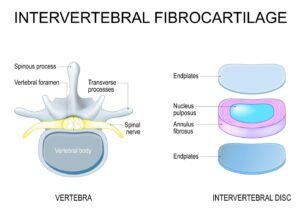

Как е изграден междупрешленният диск

Как е изграден междупрешленният диск

За да се разбере по-добре какво представлява дисковата херния, е важно да се знае как е устроен междупрешленният диск.

Дискът се състои от две основни части:

Фиброзен пръстен

Това е външната, по-здрава част на диска. Тя има стабилизираща функция и задържа вътрешното съдържимо на диска.

Пулпозно ядро

Това е вътрешната, по-мека и по-еластична част. То помага на диска да разпределя натоварването и да действа като амортисьор.

Когато дискът е здрав, тези структури работят балансирано. При дегенерация, хронично натоварване, травма или повтарящи се микротравми външният пръстен може да отслабне, а вътрешното ядро да започне да променя позицията си.